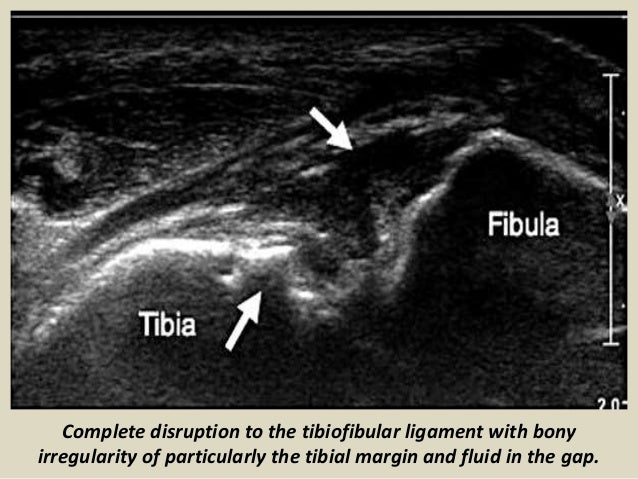

Complete disruption to the tibiofibular ligament with bony

irregularity of particularly the tibial margin and fluid in the...

74. 74. Complete disruption to the tibiofibular ligament with bony irregularity of particularly the tibial margin and fluid in the gap.